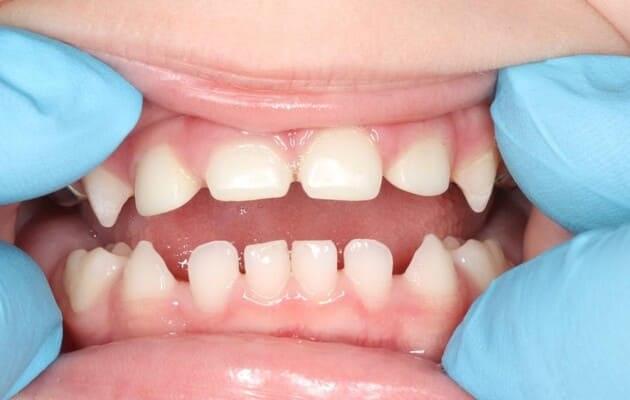

Один рік і два місяці вік дитини. Хтось скаже: «Що там тим зубам можна лікувати?!» Однак є ситуації, коли каріозний процес розвивається просто блискавично. Часто це пов’язано з порушеннями у формуванні твердих тканин ще внутрішньоутробно. А коли такі зубчики прорізуються, руйнування відбувається просто «на очах». Вісім із восьми зубів уражені, а 4 з них потребують часткового видалення пульпи («нерва»). На цьому етапі зуби вже починають турбувати і не зважаючи на юний вік дитини, зволікати не можна. Завдяки високій компетенції наших анестезіологів, які працюють з дітьми від самого народження і навіть з передчасно народженими, ми можемо проводити відповідне лікування в анестезіологічному забезпеченні за потреби навіть з першого зуба. Верхнім зубчикам, які сильно уражені, служити до 7-8 років, тому вони покриваються стандартними естетичними цирконієвими коронками, які дають максимальний результат по надійності, функції та естетиці. Година з половиною роботи і дитина може знову кусати без болю і дискомфорту. Важливо пам’ятати: для лікування зубів ніколи не буває “зарано”, це потрібно робити тоді, коли є відповідні показання